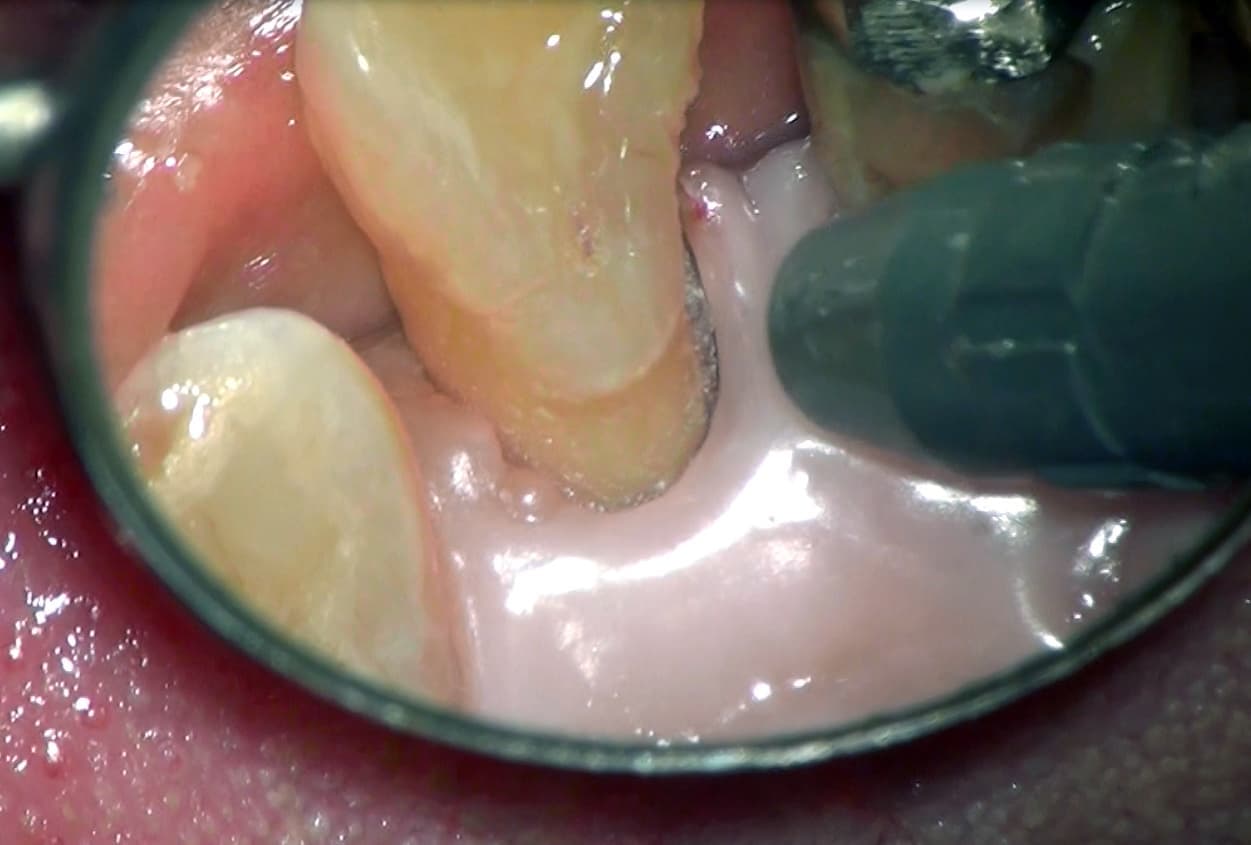

口腔内カメラ

むし歯の検査をして、奥歯や歯と歯の間にむし歯が見つかったとき、手鏡等で目を凝らして見ていただいても、見える範囲には限界があります。

口腔内カメラは、普段では見ることのできない上の奥歯の外側や親知らず、

むし歯の中も映し出すことができます。

更には、肉眼では見えないような、歯根の中のヒビまでもご覧いただくことができます。

詳細に状況を把握することにより、より的確な治療が可能となります。